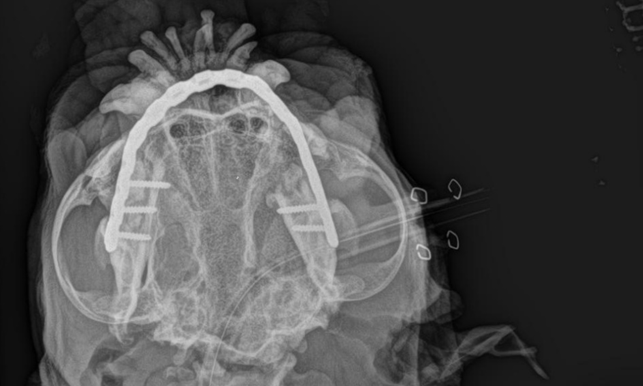

Stérilisation par cœlioscopie chez les chiennes atteintes de la maladie de von Willebrand

Histoire de Caladrius Rédigé par: Dr. Justine BRACKMAN [...]